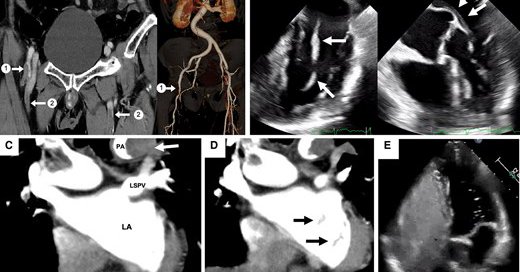

@pabloplopez_ @JGrapsa @AdrianaCMares @ErsozluSara @BenekiEirini #EHJCVI 🧠 Answer: ✅ Pulmonary arteriovenous fistula (PAVF), when paradoxical embolism is suspected without PFO, consider extracardiac RL shunts; PAVF is rare but crucial to recognize as a potential source of left-sided string-like thrombus. Read more 👉

Tweet card summary image

academic.oup.com

An 85-year-old man presented to the emergency department with right leg pain. Contrast-enhanced computed tomography (CECT) revealed occlusion of the right